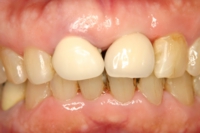

80代女性|前歯の場合

インプラント埋入